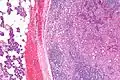

| Micrograph of an acinic cell carcinoma (right of image) and acinar glands (parotid gland - left of image). H&E stain. | |

Basophilic, bland cells similar to acinar cells. Growth pattern: solid - acinar cells, microcytic - small cystic spaces mucinous or eosinophilic, papillary-cystic - large cystic lined by epithelium, follicular - similar to thyroid tissue.

Very high mag.